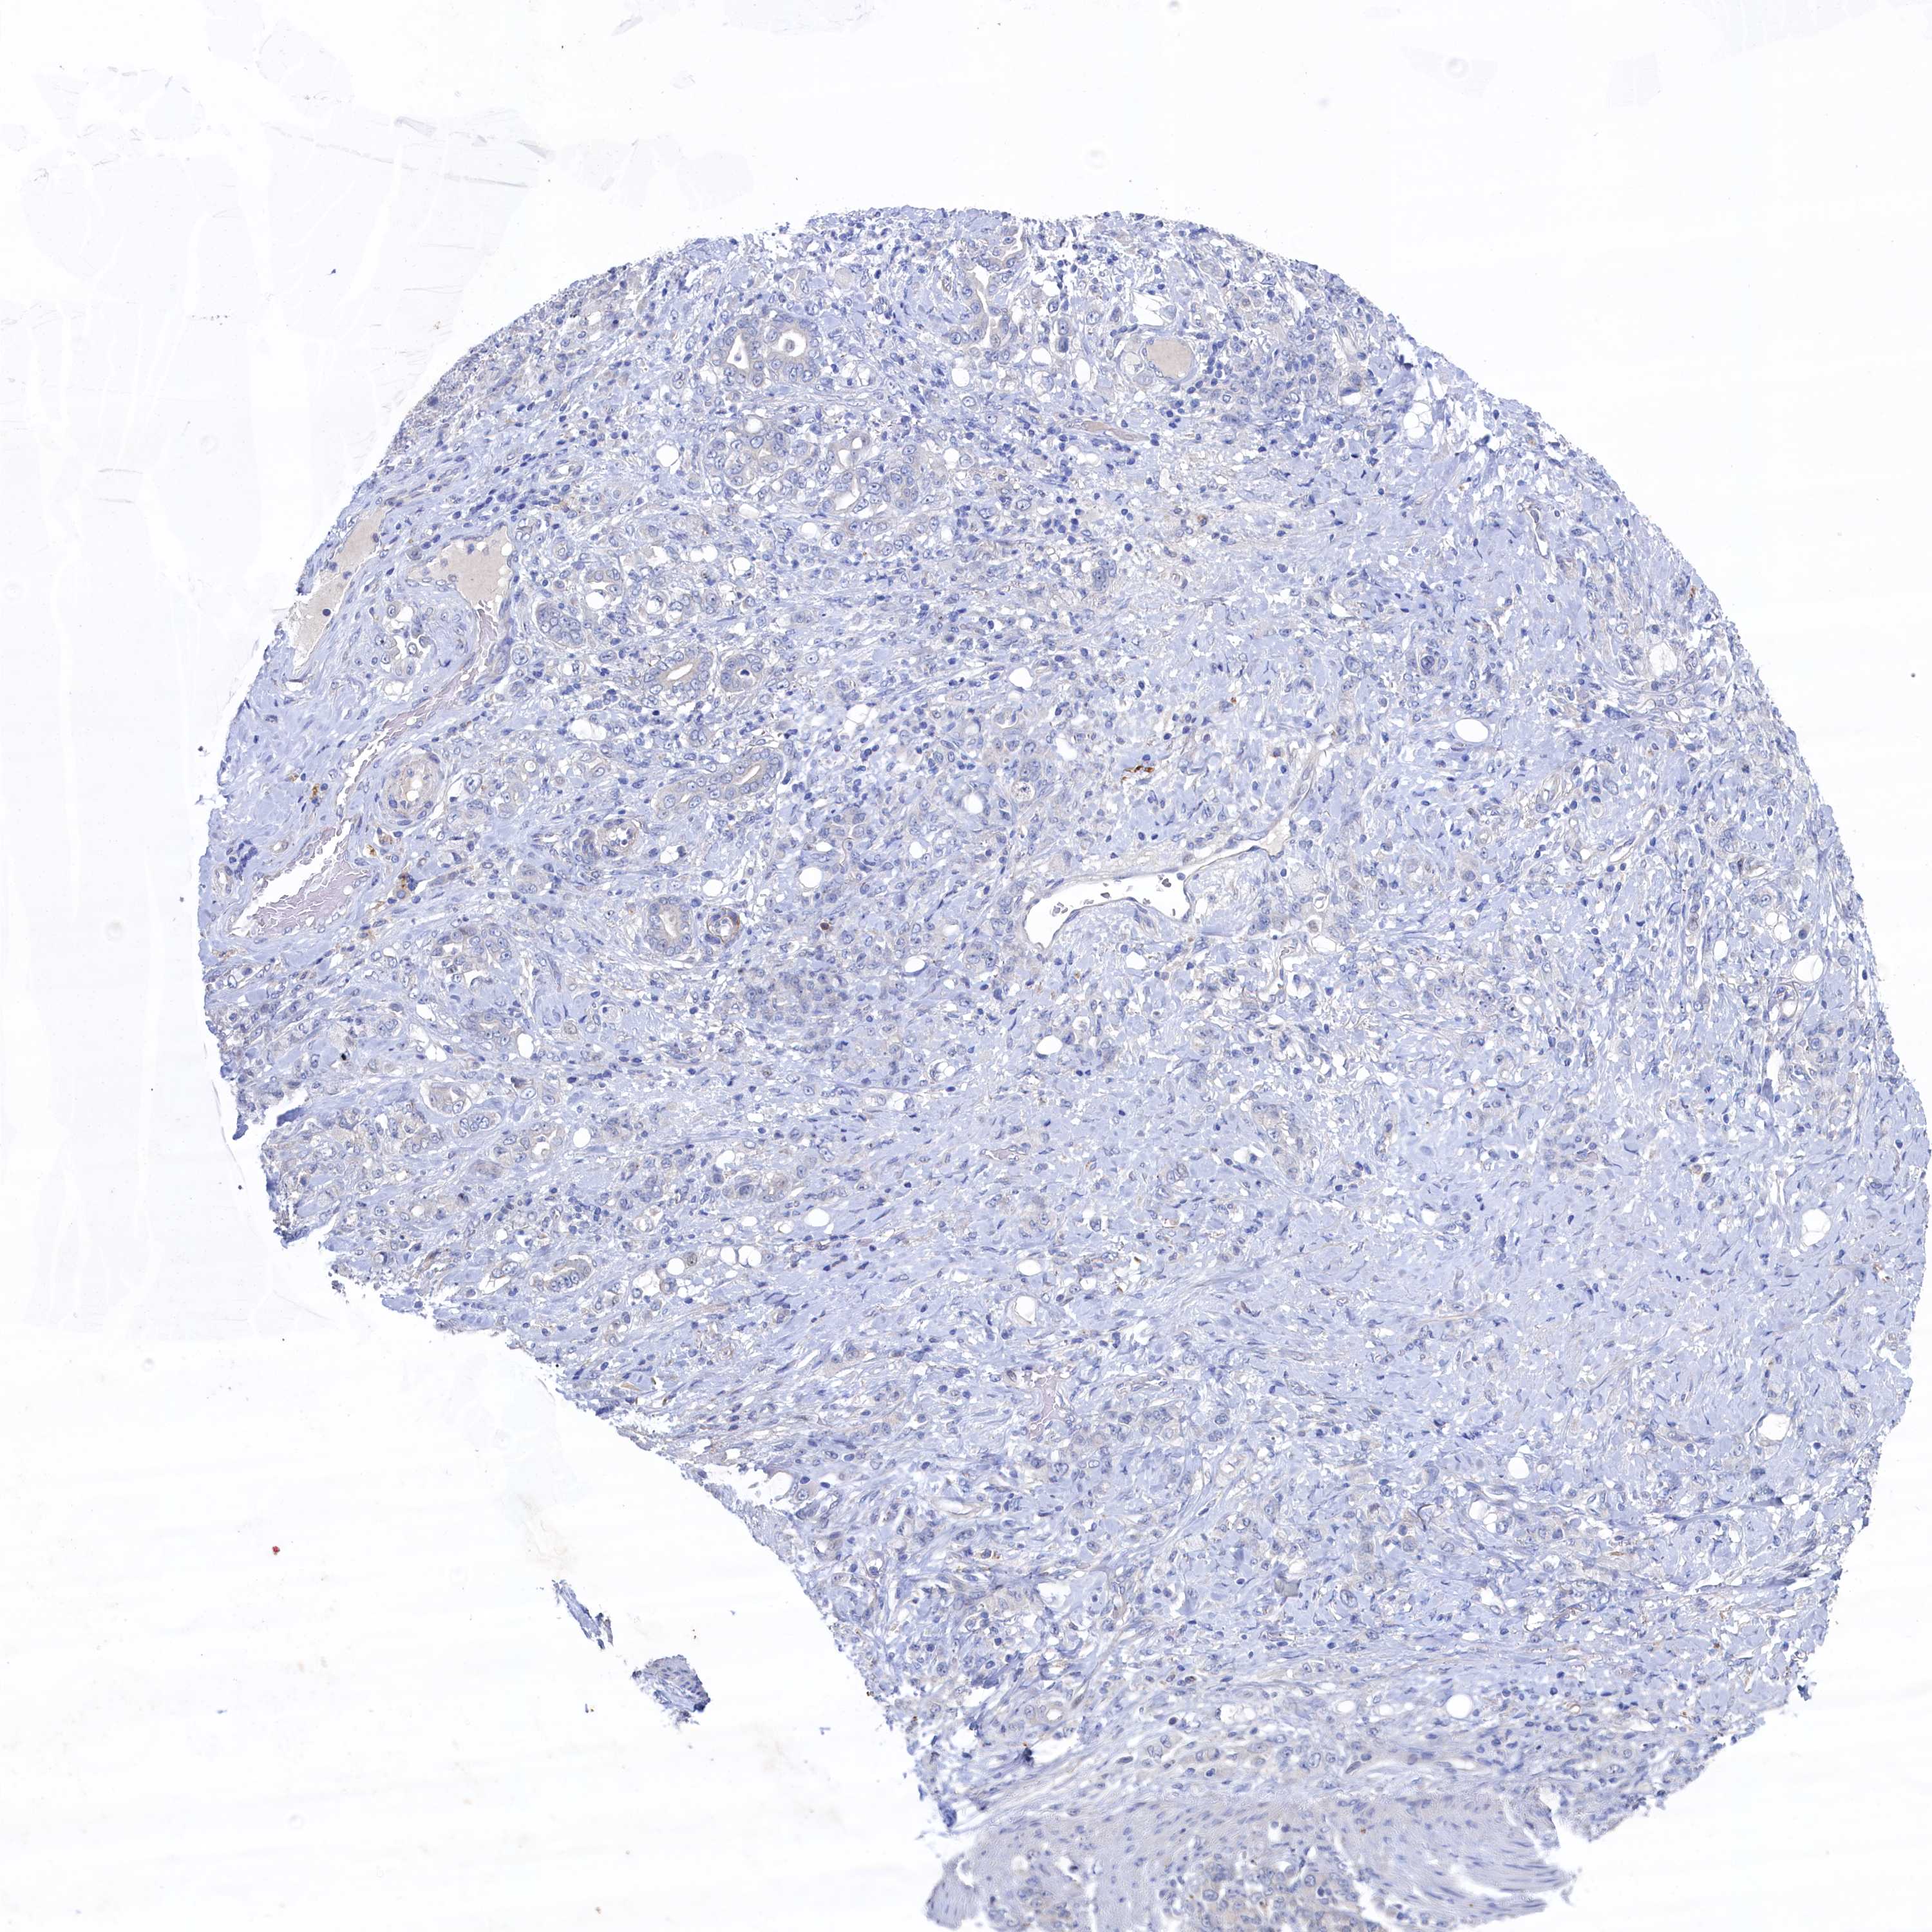

STOMACH CANCER - Protein expressioni

A mouse-over function shows sample information and annotation data. Click on an image to view it in a full screen mode. Samples can be filtered based on level of antibody staining by selecting one or several of the following categories: high, medium, low and not detected. The assay and annotation is described here.

Note that samples used for immunohistochemistry by the Human Protein Atlas do not correspond to samples in the TCGA dataset.

Antibody stainingi

Antibody staining in the annotated cell types in the current human tissue is reported as not detected, low, medium, or high, based on conventional immunohistochemistry profiling in selected tissues. This score is based on the combination of the staining intensity and fraction of stained cells.

Each image is clickable and will lead to virtual microscopy that enables deeper exploration of all samples and also displays staining intensity scores, fraction scores and subcellular localization as well as patient and tissue information for each sample.

Antibody HPA039908

Antibody HPA040774

Staining

High

Medium

Low

Not detected

Intensity

Strong

Moderate

Weak

Negative

Quantity

>75%

75%-25%

<25%

None

Location

Nuclear

Cytoplasmic/membranous

Cytoplasmic/membranous,nuclear

Adenocarcinoma, NOS

Adenocarcinoma, High grade